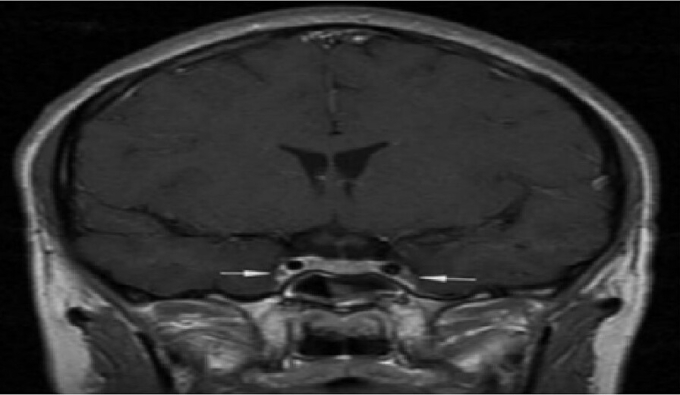

Tiến sĩ Nguyễn Hữu Quân, Trung tâm Cấp cứu A9, cho biết bệnh nhân khởi phát từ viêm xoang cấp có mủ, sau đó nhiễm trùng lan rộng gây viêm tấy nửa mặt, nhanh chóng dẫn đến rối loạn ý thức, co giật. Kết quả chụp cộng hưởng từ sọ não cho thấy hình ảnh phù nề lan tỏa, một dấu hiệu điển hình của viêm tắc tĩnh mạch xoang hang – tình trạng huyết khối nhiễm trùng hiếm gặp ở nền sọ.

Vị trí mũi tên là viêm và co thắt động mạch cảnh trong 2 bên. Ảnh: Bệnh viện cung cấp